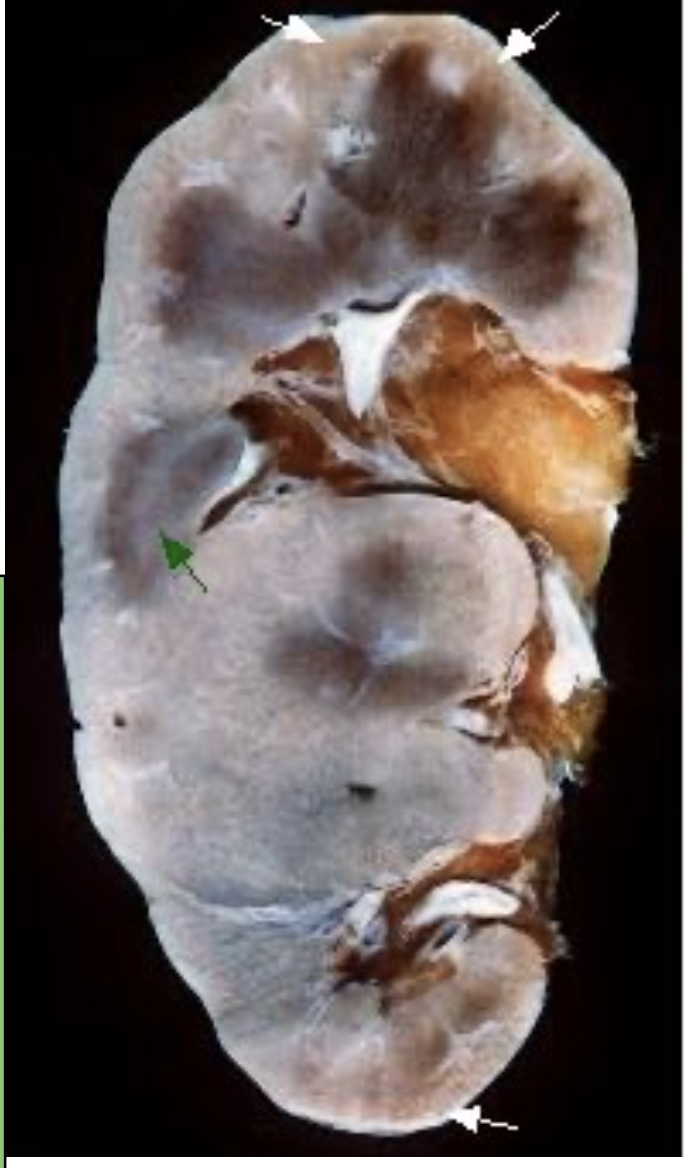

How does the gross image of the kidney appear in one with amyloidosis?

kidney generally enlarged: cortex is thickened by yellow-white deposits of amyloid white arrows and the blurry appearance of the medulla is also caused by amyloid infiltration (green arrows)